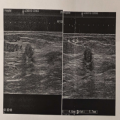

发现左乳无痛性肿块1月。 查体:双乳外观对称,发育正常,皮肤表面无红肿。左乳房发现肿块,边界不清,表面欠光滑,活动度差,无压痛。双侧腋下未及肿大淋巴结。 辅助检查:2023-05-12 13:45 乳腺专题彩超(影像号:04024932)检查报告:检查结果:左乳实性肿块,内血流稍丰富,但超声造影早期强化不明显,BI-RADS:4b类,建议手术。

影像学检查:

(点击查看大图)